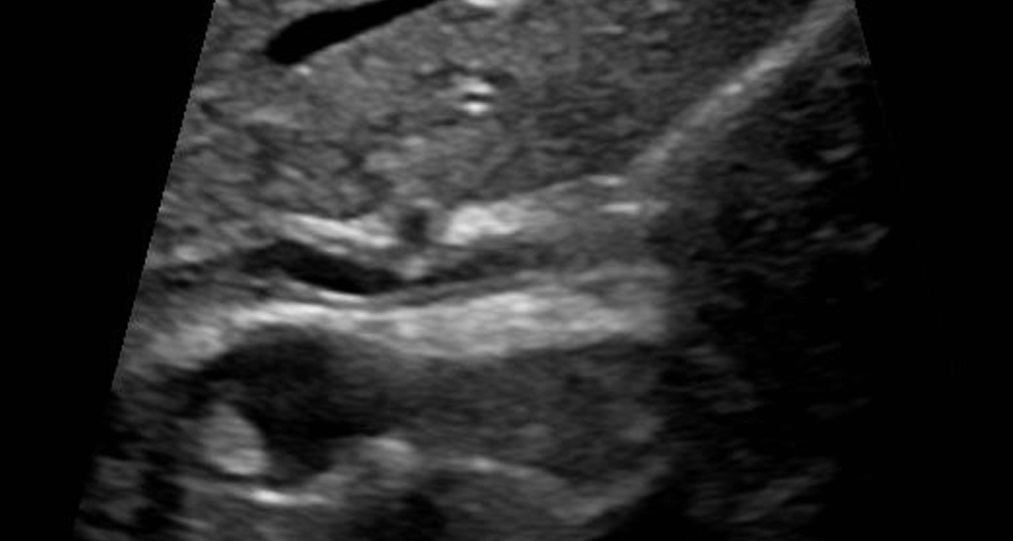

Primary Sclerosing Cholangitis

Primary sclerosing cholangitis (PSC) is inflammation and fibrosis of intrahepatic and extrahepatic bile ducts.

On contrast imaging, uninvolved areas expand, giving them a beaded look.